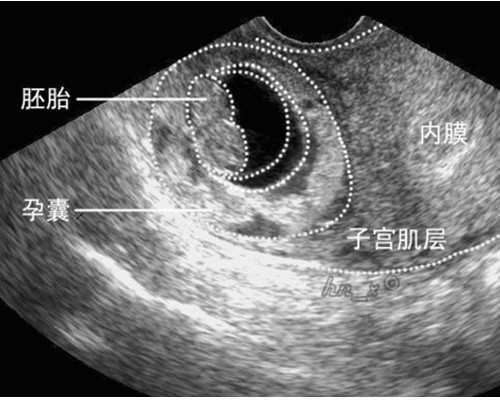

孕早期唐氏筛查是什么时候妊娠早期的唐氏筛查,包括胎儿颈后透明带B超检查和孕母血生化检查的筛查,是对胎儿染色体遗传性疾病的筛查。因为唐氏筛查准确性不高,所以通过做nt检查,早期筛查和中期唐氏筛查来提高唐氏儿的排查率。对于怀孕初期的孕妇,可以去医院通过基因筛查或者染色体的检查来检查胎儿是否存在多囊肾。